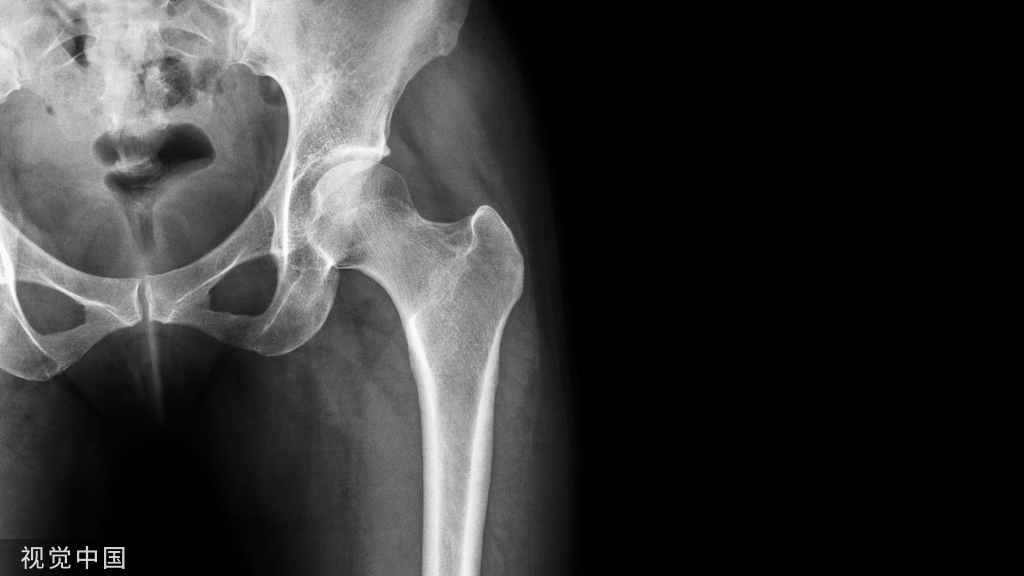

临床问题 6 对疑似老年 FFP 的患者,临床医生应选择哪些影像学检查?

推荐6 推荐拍摄正位、出口位、入口位骨盆X线片和CT冠状面、矢状位面重建(推荐分级:2B)。